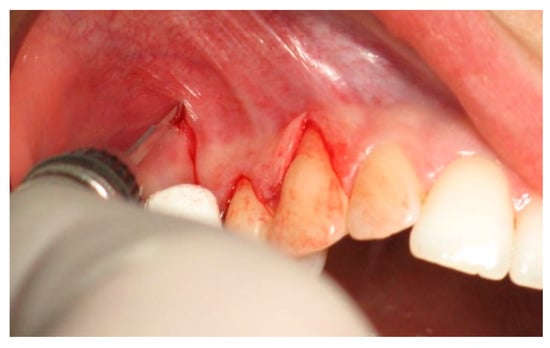

2.3. Surgical Procedures